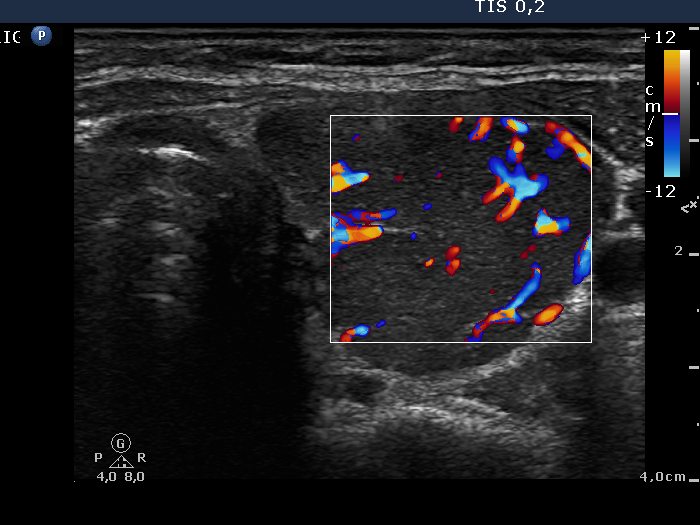

Left lobe, transverse scan. The vascularization is significantly increased.